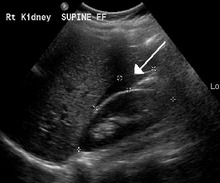

An ultrasound showing a gestational sac with fetal heart in the fallopian tube has a very high specificity of ectopic pregnancy. Transvaginal ultrasonography has a sensitivity of at least 90% for ectopic pregnancy.[4] The diagnostic ultrasonographic finding in ectopic pregnancy is an adnexal mass that moves separately from the ovary. In around 60% of cases, it is an inhomogeneous or a noncystic adnexal mass sometimes known as the "blob sign". It is generally spherical, but a more tubular appearance may be seen in case of hematosalpinx. This sign has been estimated to have a sensitivity of 84% and specificity of 99% in diagnosing ectopic pregnancy.[4] In the study estimating these values, the blob sign had a positive predictive value of 96% and a negative predictive value of 95%.[4] The visualization of an empty extrauterine gestational sac is sometimes known as the "bagel sign", and is present in around 20% of cases.[4] In another 20% of cases, there is visualization of a gestational sac containing a yolk sac or an embryo.[4] Ectopic pregnancies where there is visualization of cardiac activity are sometimes termed "viable ectopic".[4]

A small amount of anechogenic-free fluid in the recto-uterine pouch is commonly found in both intrauterine and ectopic pregnancies.[4] The presence of echogenic fluid is estimated at between 28 and 56% of women with an ectopic pregnancy, and strongly indicates the presence of hemoperitoneum.[4] However, it does not necessarily result from tubal rupture but is commonly a result from leakage from the distal tubal opening.[4] As a rule of thumb, the finding of free fluid is significant if it reaches the fundus or is present in the vesico-uterine pouch.[4] A further marker of serious intra-abdominal bleeding is the presence of fluid in the hepatorenal recess of the subhepatic space.[4]